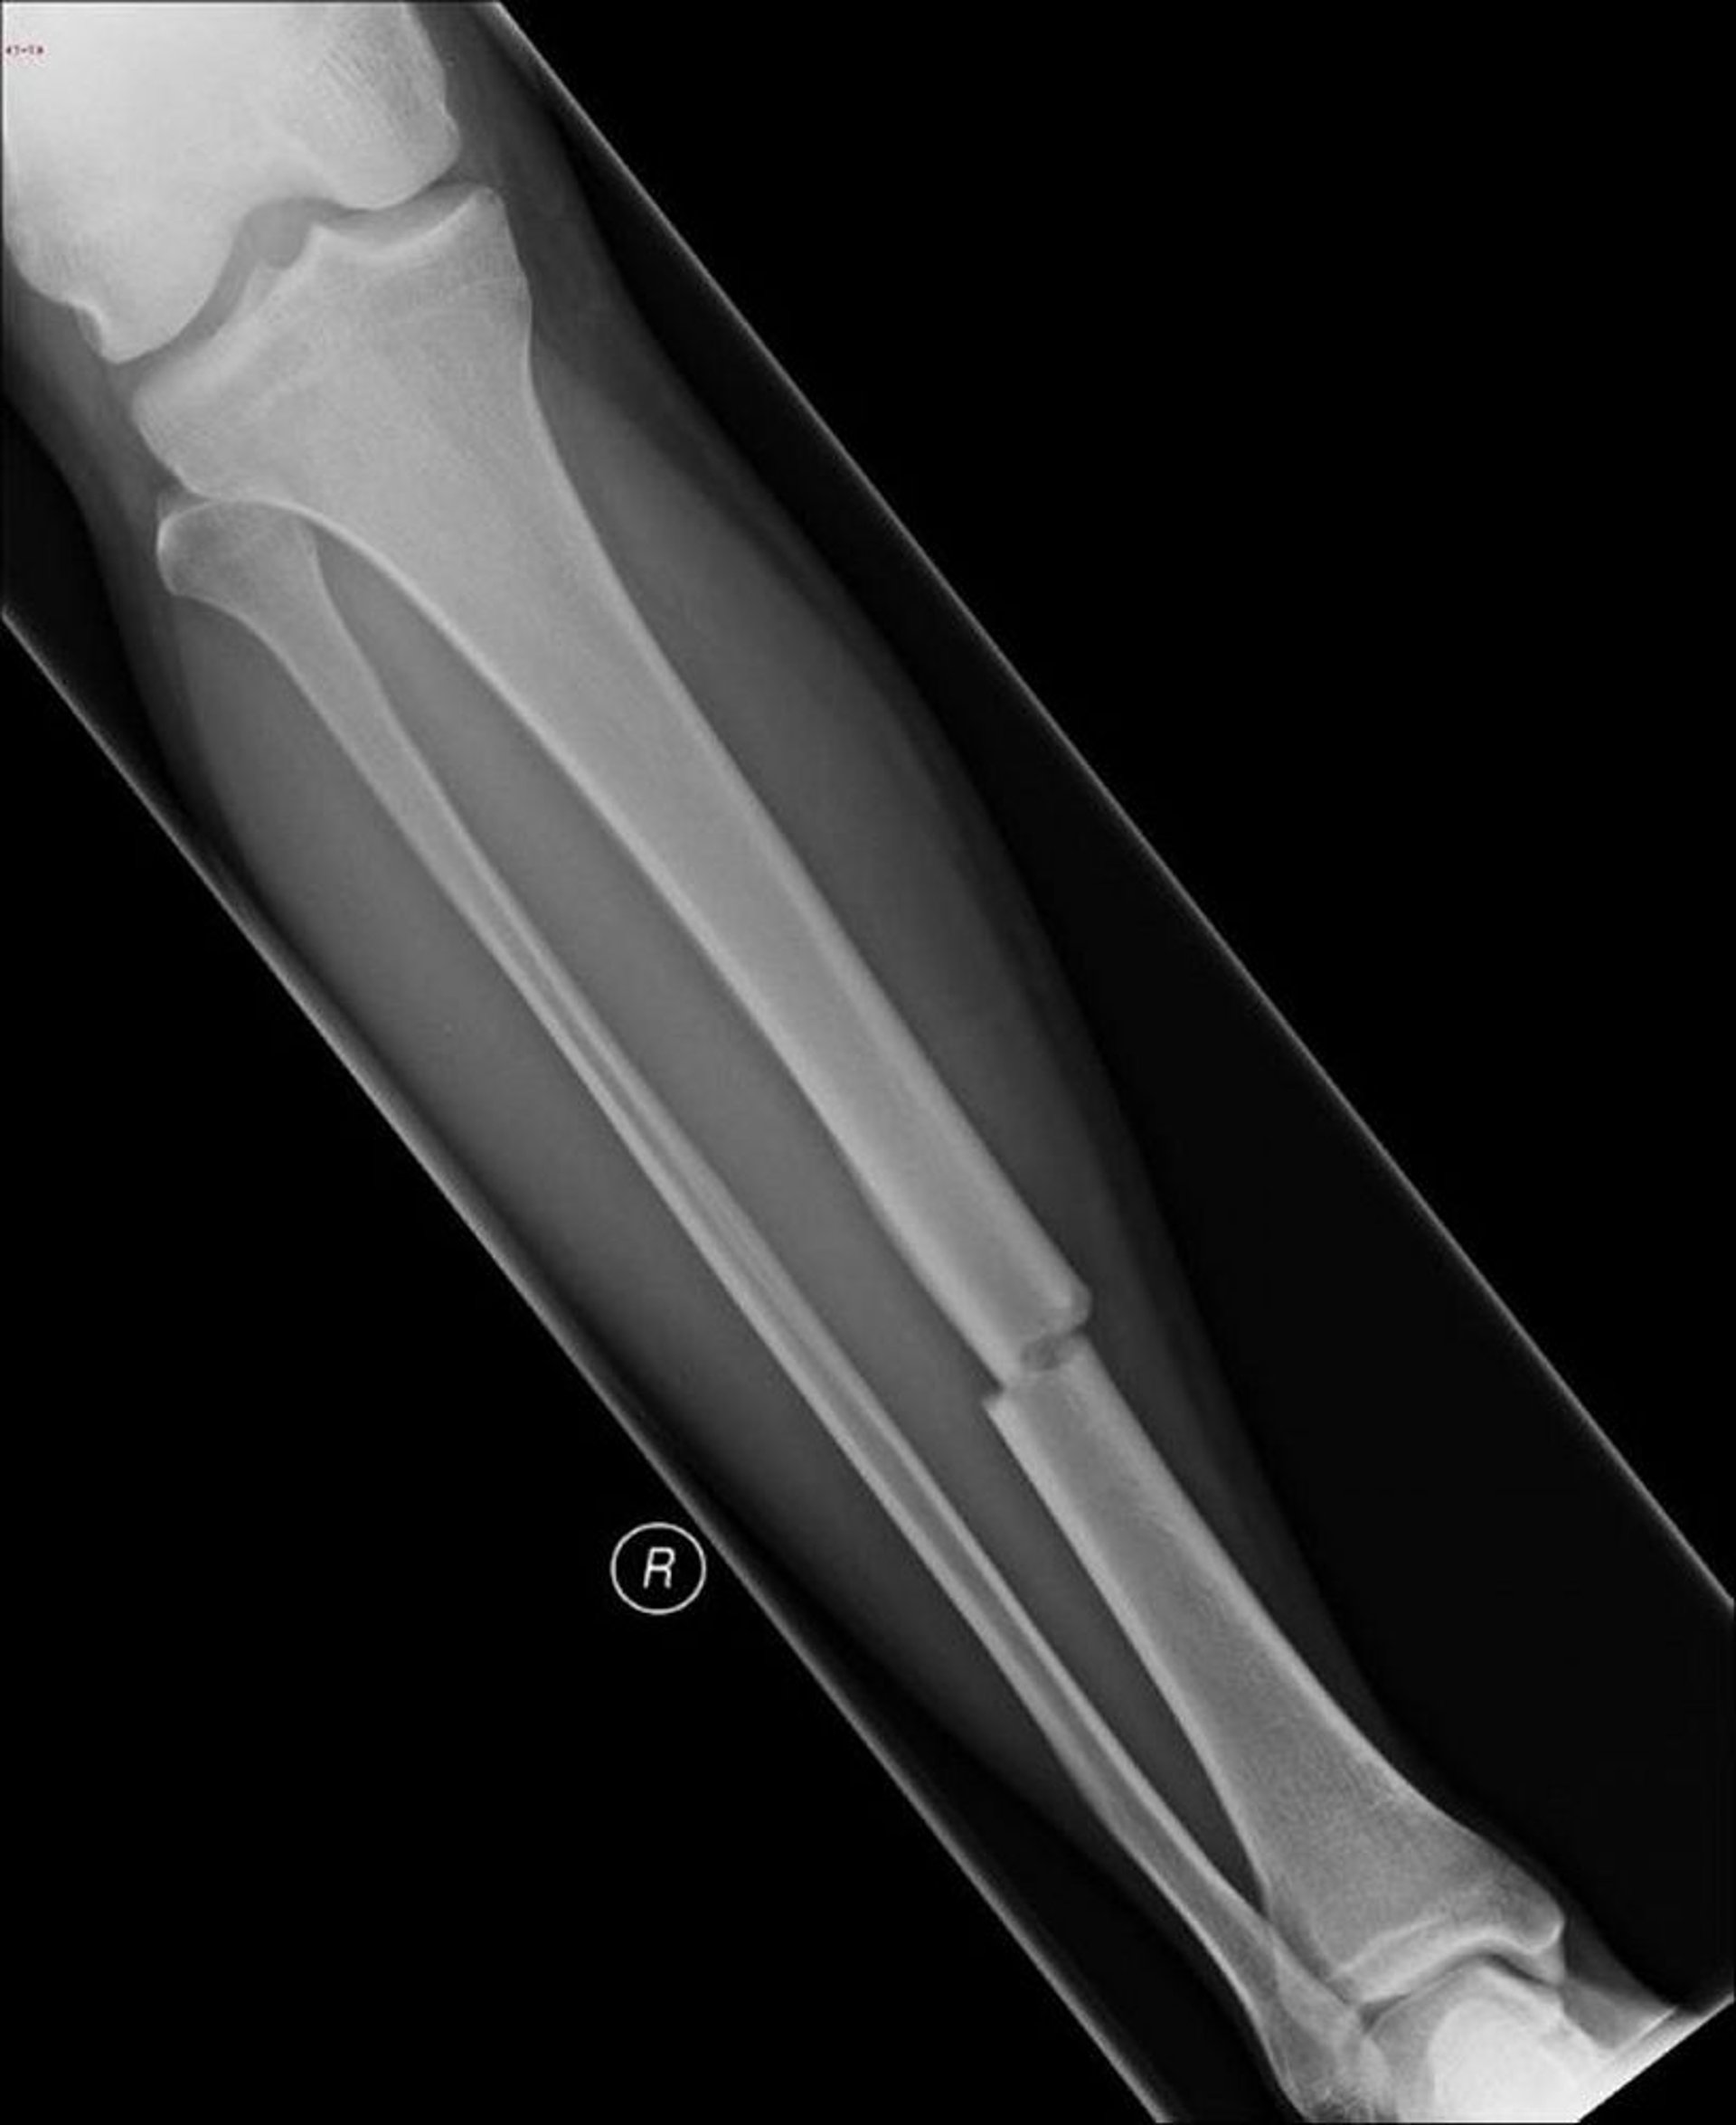

脛骨骨幹部の横骨折

この横骨折は脛骨の骨幹部に生じている。

Image courtesy of Danielle Campagne, MD.